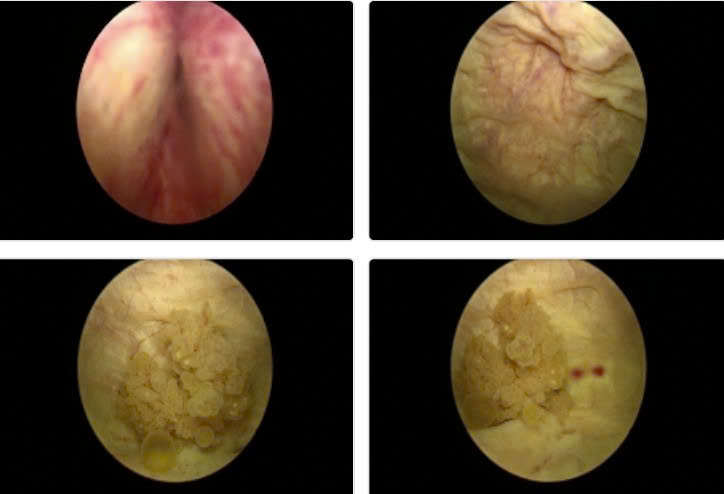

Hình ảnh nội soi u bàng quang vị trí sát lỗ niệu quản trái kích thước 2cm, có chỉ định phẫu thuật nội soi cắt u bàng quang sớm để chẩn đoán tế bào học.